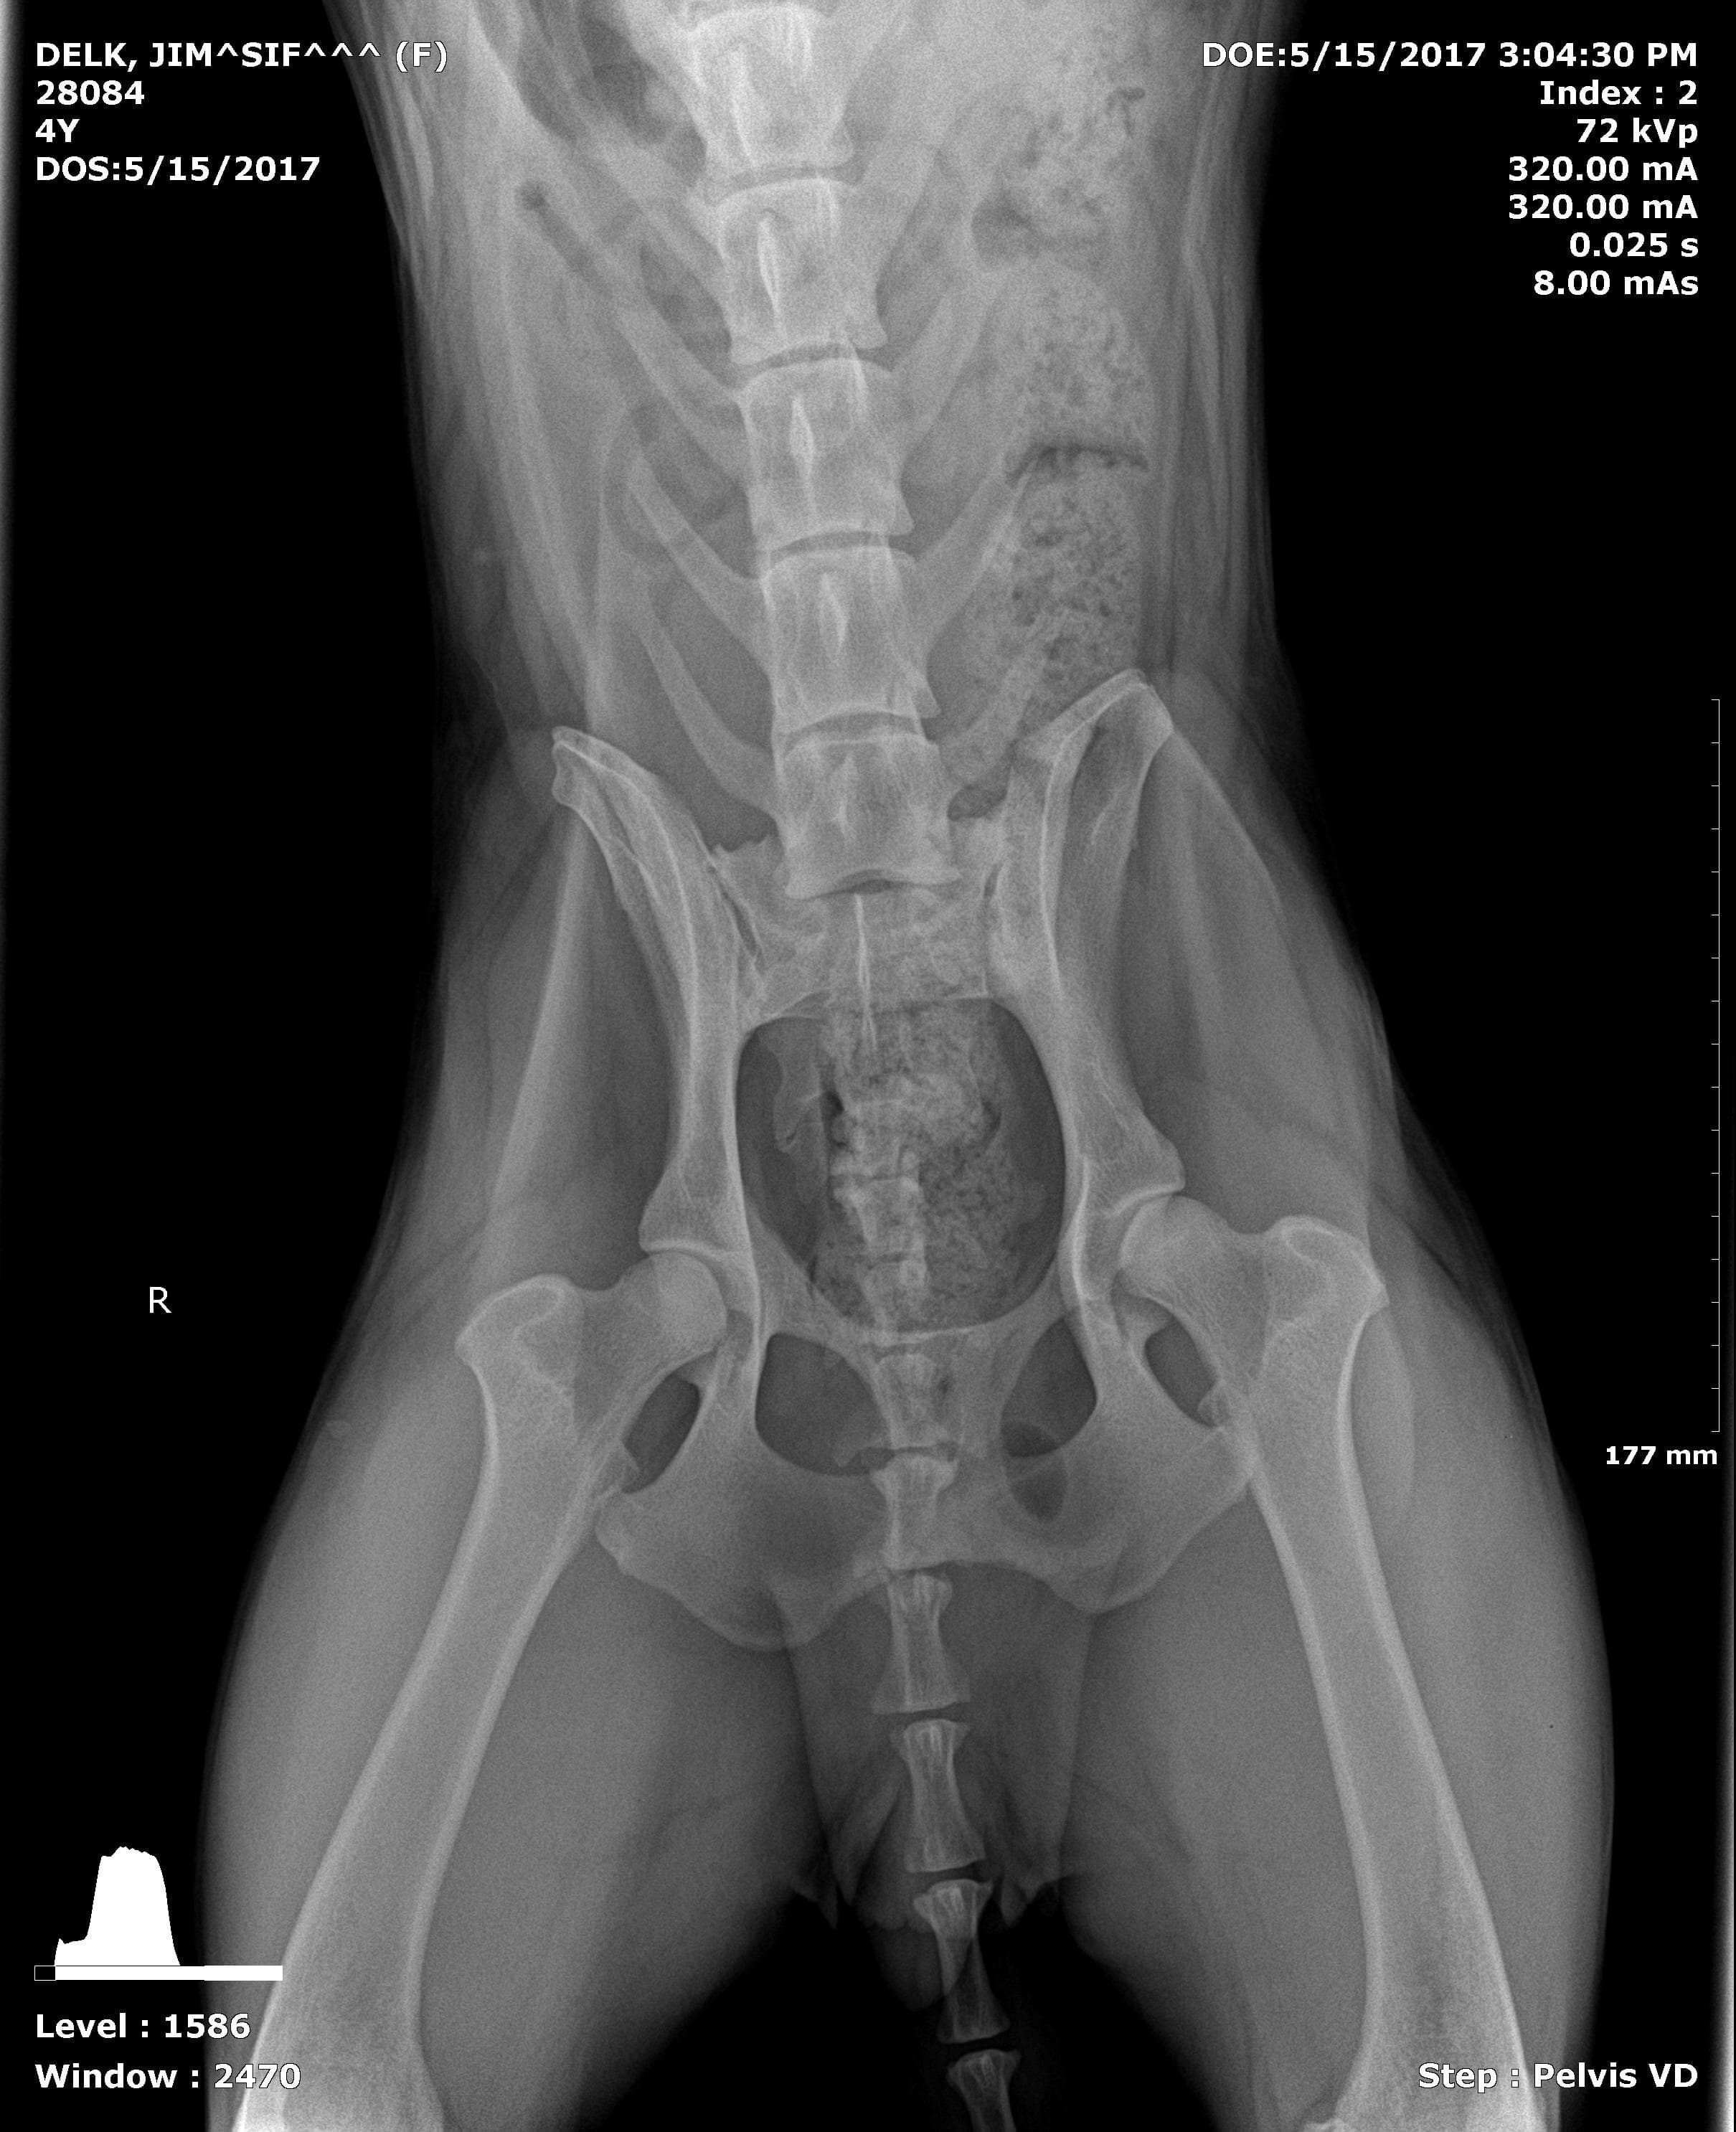

My dog doesn't have full function of her back right leg and will not correct it if it is moved out of place. We were referred to LSU for an MRI. Is there any other issues that she could have other than degenerative myelopathy? We are so scared we are going to lose our baby. She is a German Shepherd, six years old.

While degenerative myelopathy is a concern giving your dogs breed and these clinical signs there are other possible causes. The MRI could help show if there could be an infection affecting the spinal cord, or herniated disc, or even some sort of mass that could be potential be removed. While none of those sound like good alternatives some of them may be curable or even manageable longer than to degenerative myelopathy.